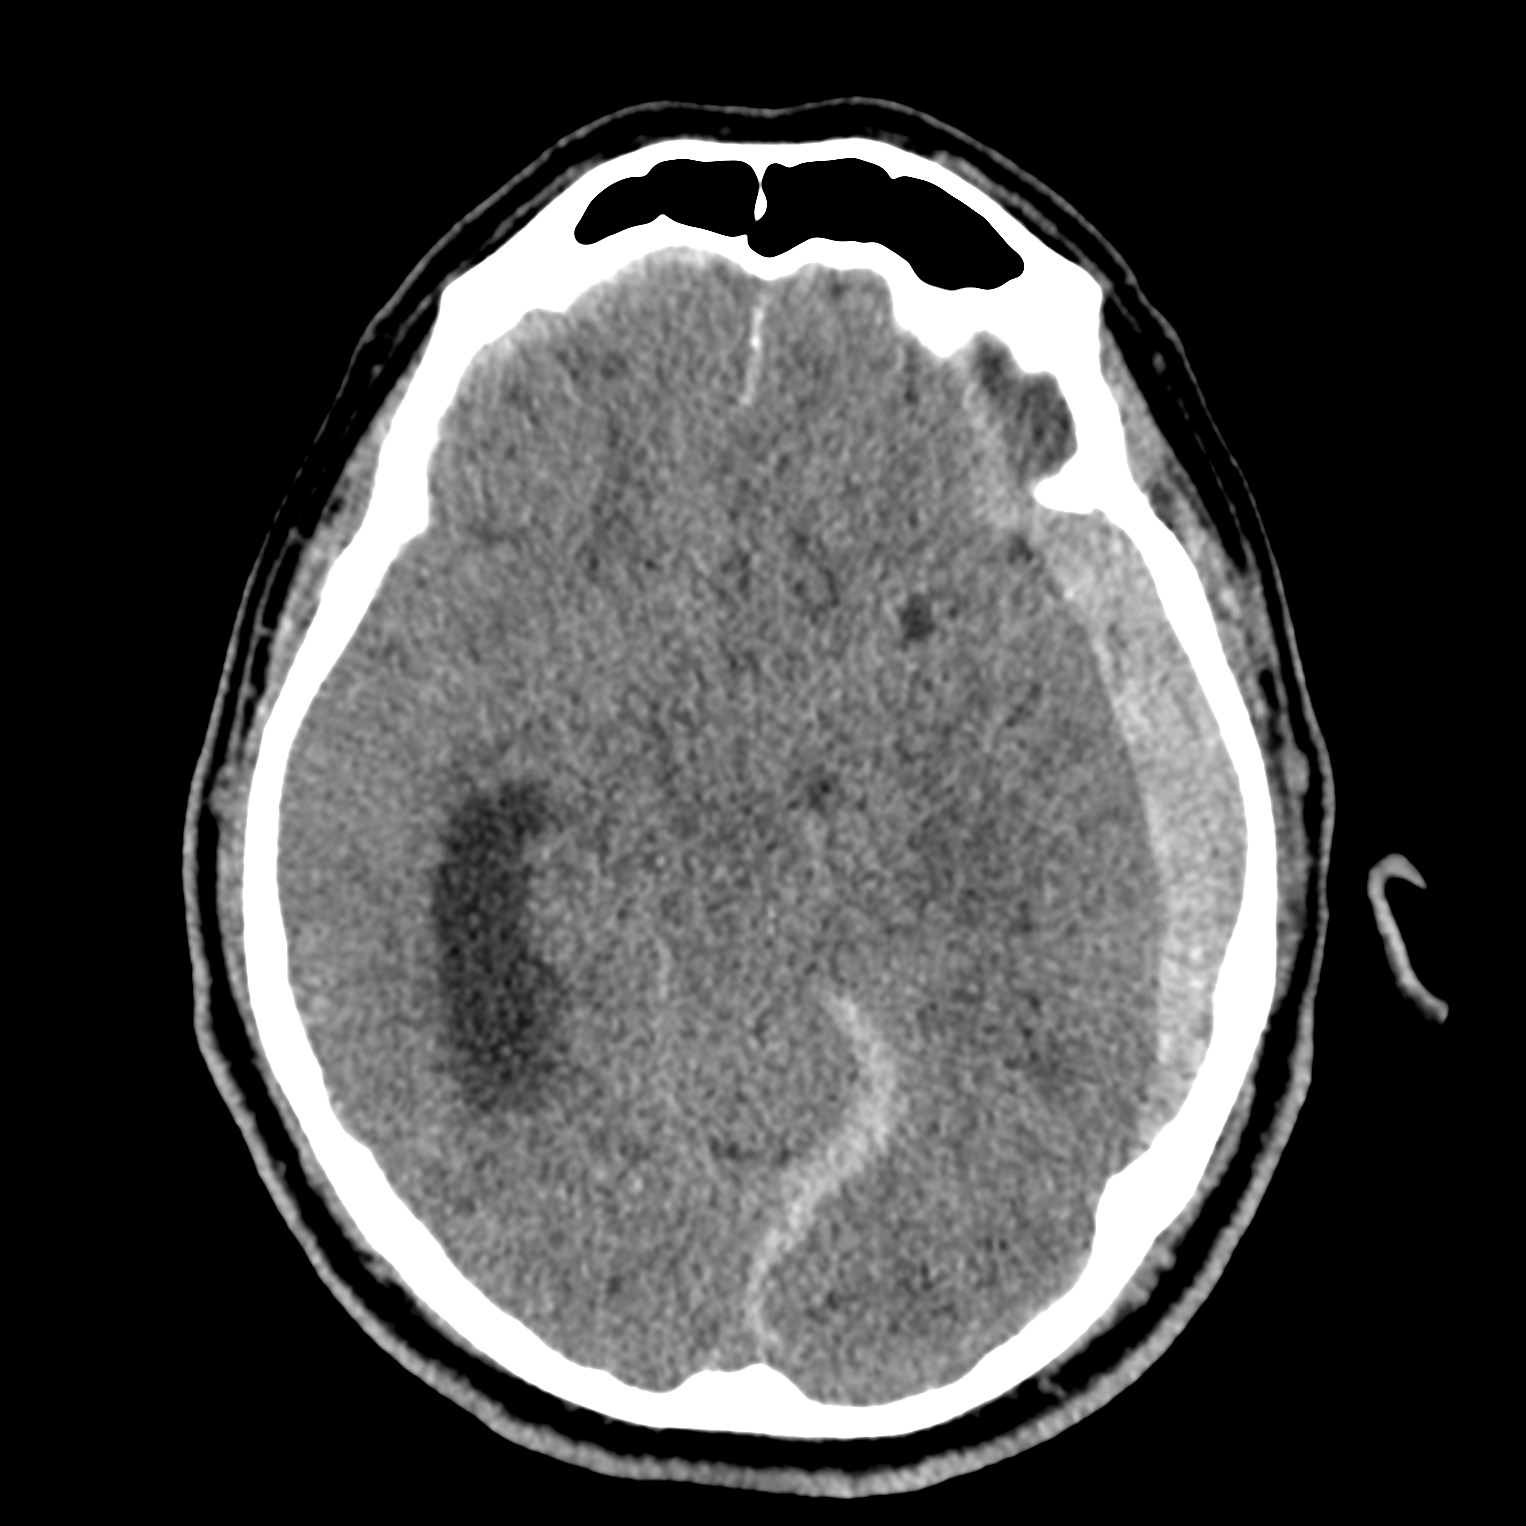

ちなみに画像診断とは、CTやMRIなどの画像を見て、正常か異常か、異常であればそれが何なのかを診断する仕事です。

Case courtesy of Andrew Dixon, Radiopaedia.org. From the case rID: 32383

医療従事者でなければ何のメリットも無いかもしれないのですが、実際の画像を自分でスクロールしながら学ぶことができるというのは、ものすごく大きなことだと思います。

さらに症例の解説を付け加えたら、読影能力アップのための強力なツールになるのではないかと期待しています。